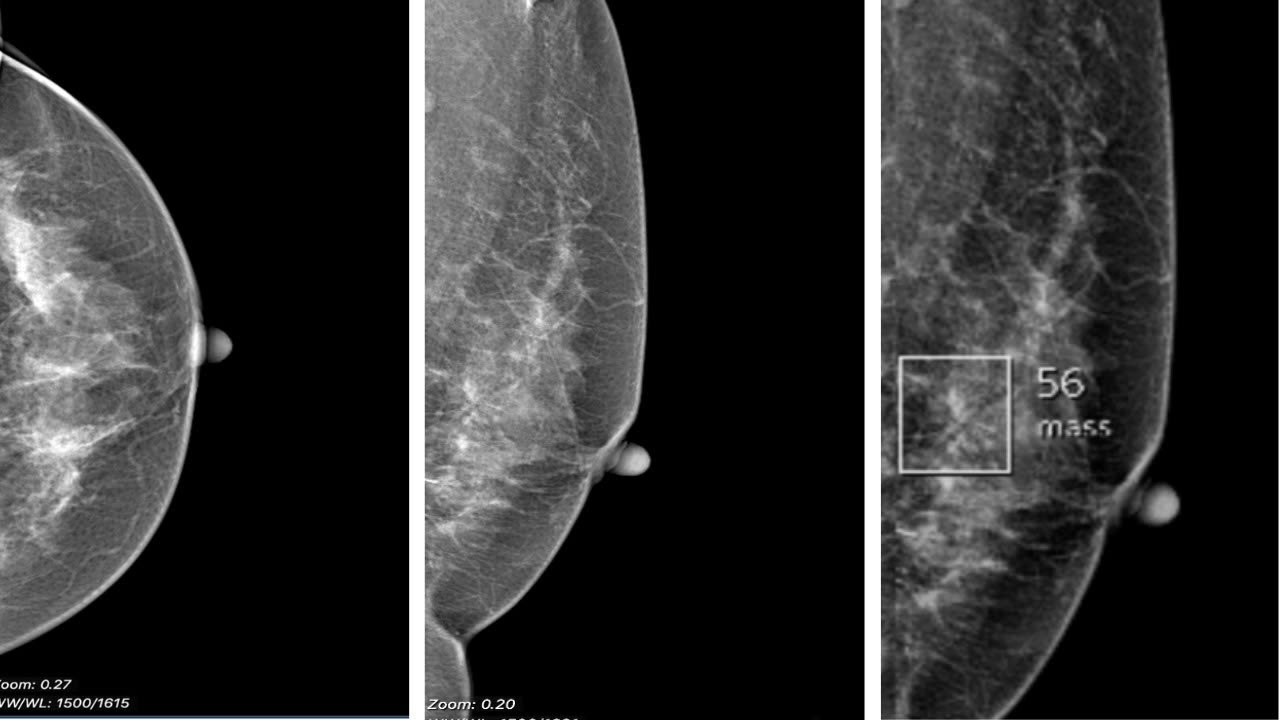

Hình ảnh phim chụp Xquang tuyến vú trái của bệnh nhân H theo hướng CC và MLO có tổn thương nhỏ được phát hiện bới AI.

Khi hình ảnh được phân tích bằng phần mềm trí tuệ nhân tạo (AI), hệ thống đã phát hiện một vùng biến đổi cấu trúc mô vú rất nhỏ và kín đáo. Các bác sĩ đã tiến hành chụp ép phóng đại tập trung vào khu vực nghi ngờ, và trên hình ảnh phóng đại, tổn thương trở nên rõ nét hơn rất nhiều.